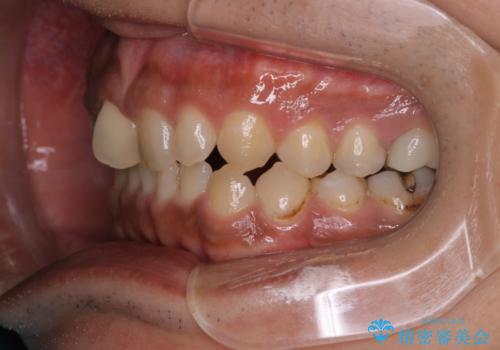

【モニター】インビザライン 前歯の捻れを治したい

- 30代男性

- 矯正装置

- インビザライン

- 上下の前歯のがたつきを主訴に来院されました。インビザラインで治療可能と判断致しましたので、IPR(歯と歯の間を削る処置)と歯列弓拡大をして

がたつきをとる治療計画を立てました。

マウスピースをしっかり使用していただいたことで、主訴である前歯のがたつきも改善され

リファイメントも1回のみで治療を終了することが出来ました。